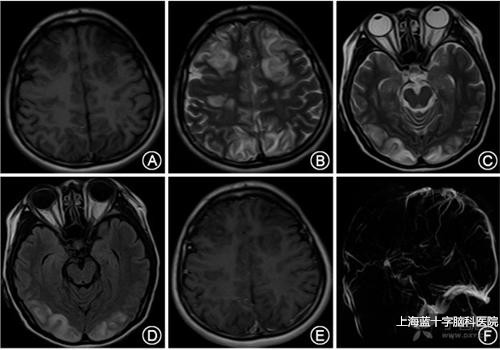

脑静脉窦血栓形成的临床表现复杂而不典型,取决于其受累范围、部位以及血栓活性。一个较大的原发性血栓常导致一系列症状如头痛、颅高压、晕沉、眼部的不适(包括视力障碍和眼胀、或结膜充血)、癫痫、神经功能障碍、耳鸣脑鸣和颈部不适等。具体分述如下:

2.颅内静脉窦血栓形成的临床表现缺乏特异性,其症状体征表现各异,急性起病,也可历经数周缓慢起病。最常见的症状包括头痛,局灶性神经功能缺损、癫痫发作意识障碍视盘水肿等。